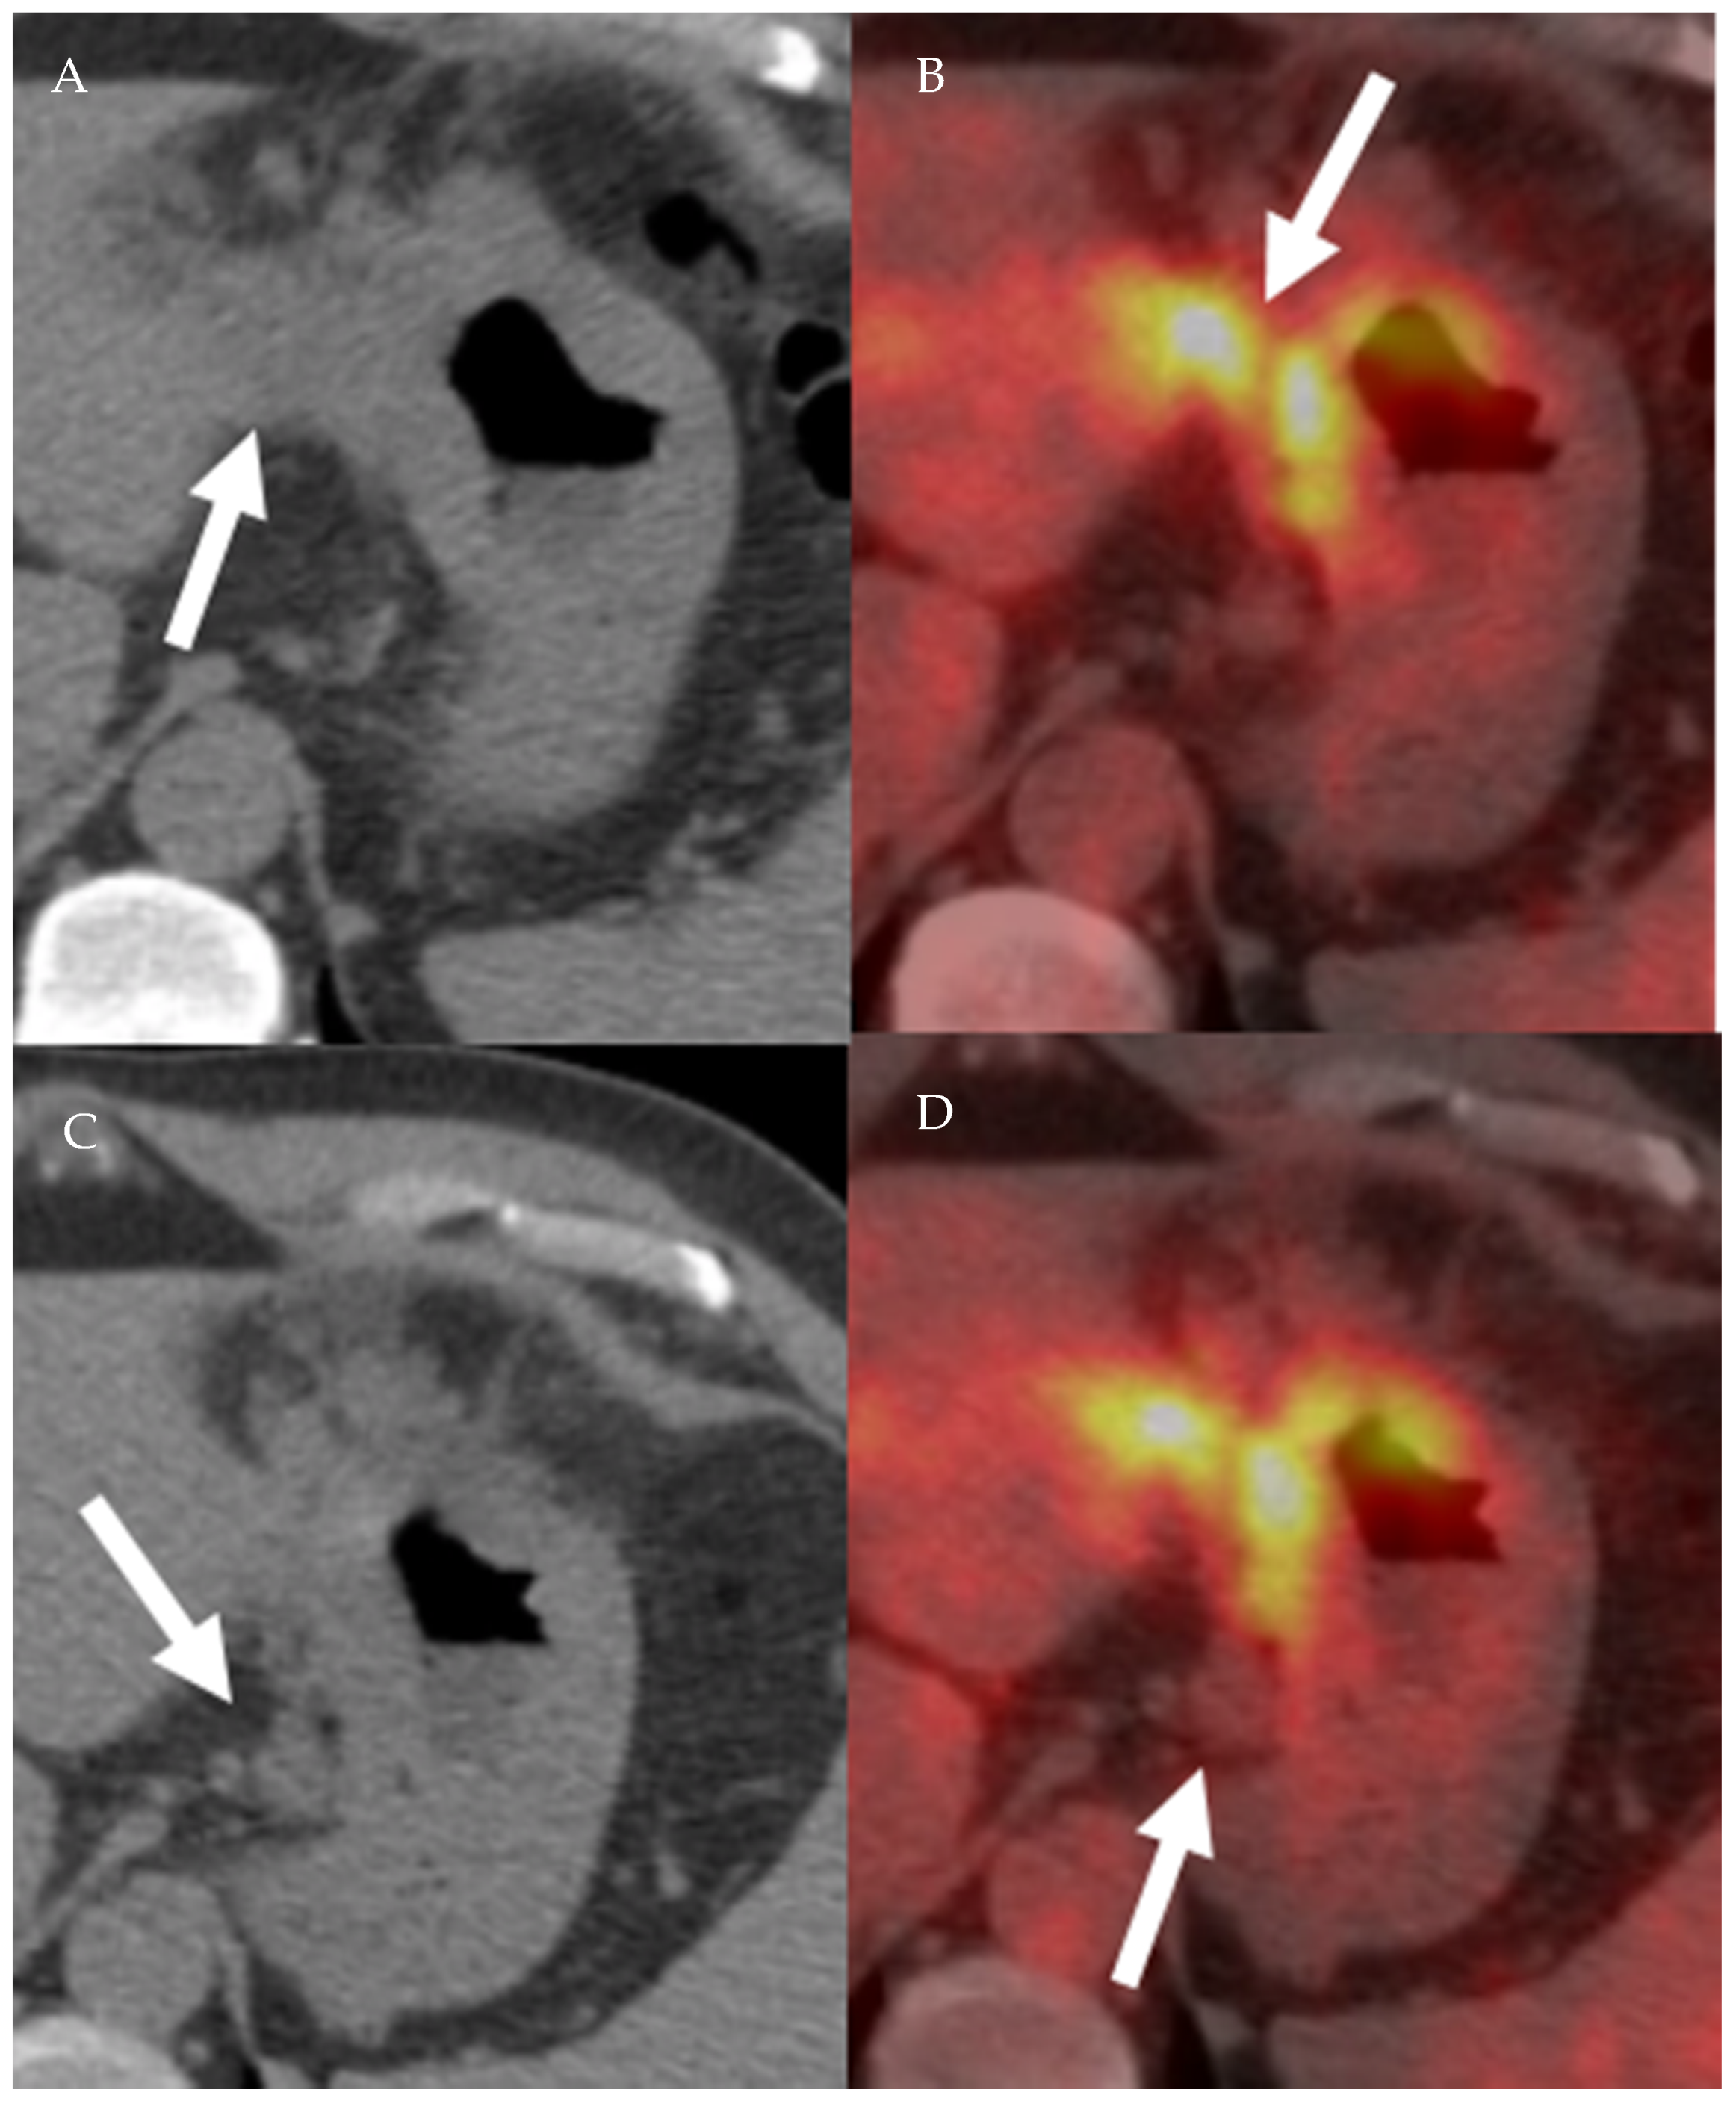

- Mittra, E.; Quon, A. Positron Emission Tomography/Computed Tomography: The Current Technology and Applications. Radiol. Clin. N. Am. 2009, 47, 147–160. [Google Scholar] [CrossRef]

- Vallabhajosula, S. 18F-Labeled Positron Emission Tomographic Radiopharmaceuticals in Oncology: An Overview of Radiochemistry and Mechanisms of Tumor Localization. Semin. Nucl. Med. 2007, 37, 400–419. [Google Scholar] [CrossRef] [PubMed]

- Liu, B.; Gao, S.; Li, S. A Comprehensive Comparison of CT, MRI, Positron Emission Tomography or Positron Emission Tomogra-phy/CT, and Diffusion Weighted Imaging-MRI for Detecting the Lymph Nodes Metastases in Patients with Cervical Cancer: A Me-ta-Analysis Based on 67 Studies. Gynecol. Obstet. Investig. 2017, 82, 209–222. [Google Scholar] [CrossRef] [PubMed]

- Choi, H.J.; Ju, W.; Myung, S.-K.; Kim, Y. Diagnostic performance of computer tomography, magnetic resonance imaging, and positron emission tomography or positron emission tomography/computer tomography for detection of metastatic lymph nodes in patients with cervical cancer: Meta-analysis. Cancer Sci. 2010, 101, 1471–1479. [Google Scholar] [CrossRef]

- Riegger, C.; Koeninger, A.; Hartung, V.; Otterbach, F.; Kimmig, R.; Forsting, M.; Bockisch, A.; Antoch, G.; Heusner, T.A. Comparison of the Diagnostic Value of FDG-PET/CT and Axillary Ultrasound for the Detection of Lymph Node Metastases in Breast Cancer Patients. Acta Radiol. 2012, 53, 1092–1098. [Google Scholar] [CrossRef] [PubMed]

- Cochet, A.; Dygai-Cochet, I.; Riedinger, J.-M.; Humbert, O.; Berriolo-Riedinger, A.; Toubeau, M.; Guiu, S.; Coutant, C.; Coudert, B.; Fumoleau, P.; et al. 18F-FDG PET/CT provides powerful prognostic stratification in the primary staging of large breast cancer when compared with conventional explorations. Eur. J. Nucl. Med. Mol. Imaging 2014, 41, 428–437. [Google Scholar] [CrossRef]